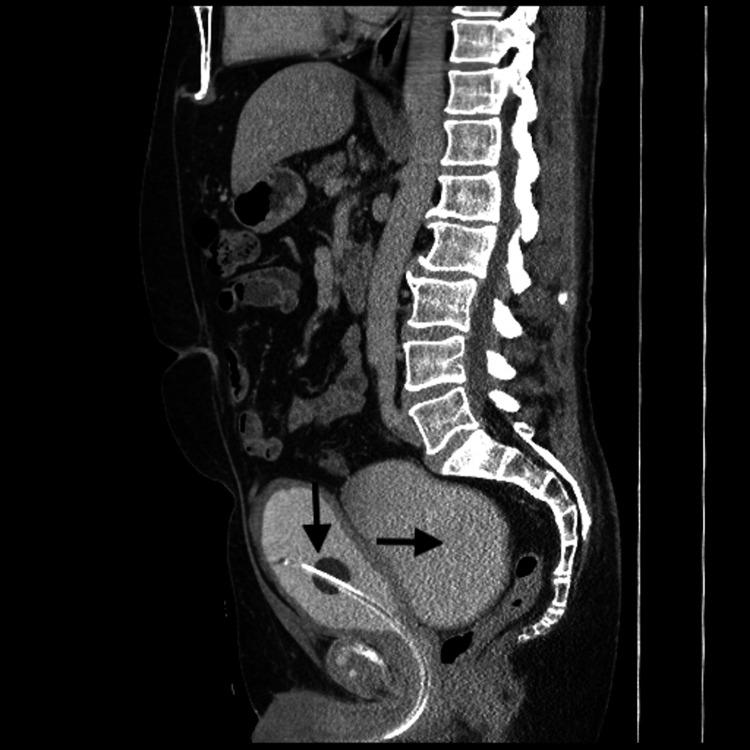

我们有6例患者接受了RBD手术;中位年龄和体重指数(BMI)分别为63.8岁(范围48 - 73岁)和27.1kg/m²(范围24 - 32)。最常见的症状是难治性LUTS和复发性尿路感染(UTIs)。尿动力学评估显示这些患者存在多种不同结果,如膀胱出口梗阻(BOO)、顺应性差以及读数不明确等情况。所有患者均报告有膀胱排空不完全和二次排尿现象,其中半数患者进行清洁间歇性自我导尿(CISC)。憩室大小平均为9.4cm(范围8.5 - 12cm)。中位手术时间和失血量分别为166分钟(范围150 - 180分钟)和75毫升(范围50 - 100毫升)。平均住院时间为1.6天(范围1 - 3天)。3例患者在术后1个月内发生UTIs,需要口服抗生素治疗。术后残余尿量(PVR)平均为32.6毫升(范围0 - 161毫升),术前平均为249毫升(范围125 - 400毫升),双尾p值为0.016。这些患者的国际前列腺症状评分(IPSS)术前平均为27.83(范围24 - 31),术后平均为8(范围7 - 12),双尾p值为0.0001。最终组织学检查未发现恶性病变,所有患者均报告症状改善,术后无人需要进行CISC。

https://cdn.ncbi.nlm.nih.gov/pmc/blobs/9890/10445242/e6141bb88256/cureus-0015-00000042354-i01.jpg